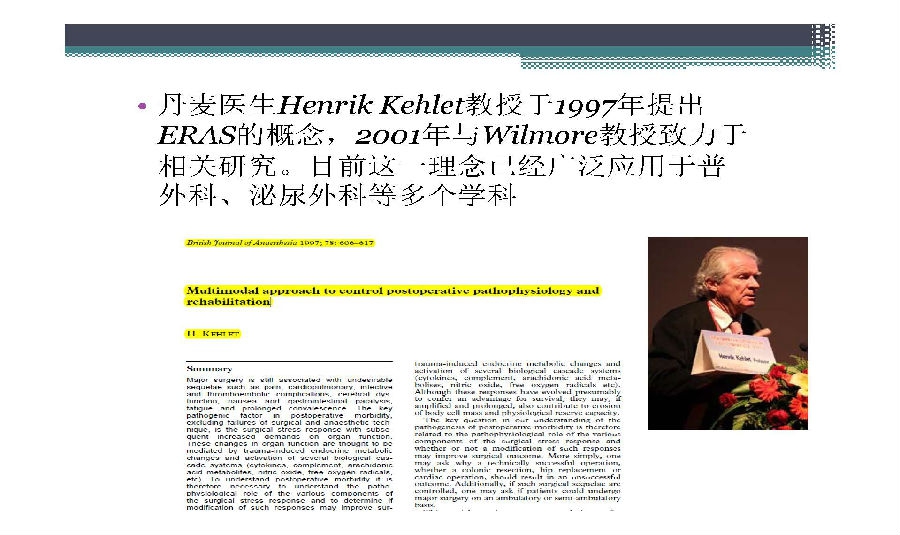

快速康复外科理念于上世纪90年代由丹麦医生提出,其核心是在围术期应用各种已被证实有效的方法以减少患者的手术应激反应和并发症,缩短住院时间,提高患者满意度,减少住院费用。国外骨科引入快速康复理念已经比较成熟,国内骨科快速康复开始相对较晚,对于中国骨科医生来说也是一个新的领域。